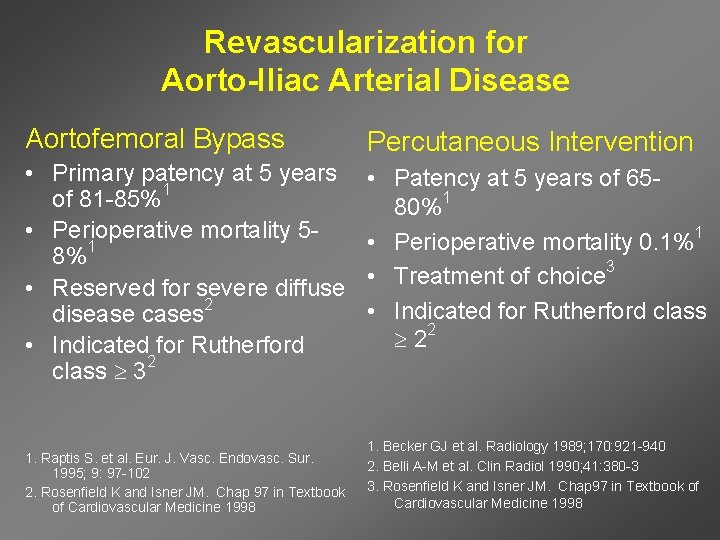

Revascularization for Aorto-Iliac Arterial Disease Aortofemoral Bypass Percutaneous Intervention • Primary patency at 5 years of 81 -85%1 • Perioperative mortality 58%1 • Reserved for severe diffuse disease cases 2 • Indicated for Rutherford class 32 • Patency at 5 years of 6580%1 • Perioperative mortality 0. 1%1 • Treatment of choice 3 • Indicated for Rutherford class 22 1. Raptis S. et al. Eur. J. Vasc. Endovasc. Sur. 1995; 9: 97 -102 2. Rosenfield K and Isner JM. Chap 97 in Textbook of Cardiovascular Medicine 1998 1. Becker GJ et al. Radiology 1989; 170: 921 -940 2. Belli A-M et al. Clin Radiol 1990; 41: 380 -3 3. Rosenfield K and Isner JM. Chap 97 in Textbook of Cardiovascular Medicine 1998